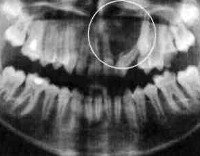

Рентгенографически при раке челюсти обнаруживают диффузное разрежение кости. Репаративной, а также периостальной реакции не наблюдается. Для подтверждения диагноза показано цитологическое исследование материала, взятого с поверхности язвы. При первичном раке челюсти проводят патогистологический анализ трепанированного участка пораженной кости. Для выявления злокачественной опухоли также может быть использован радиоизотопный метод.